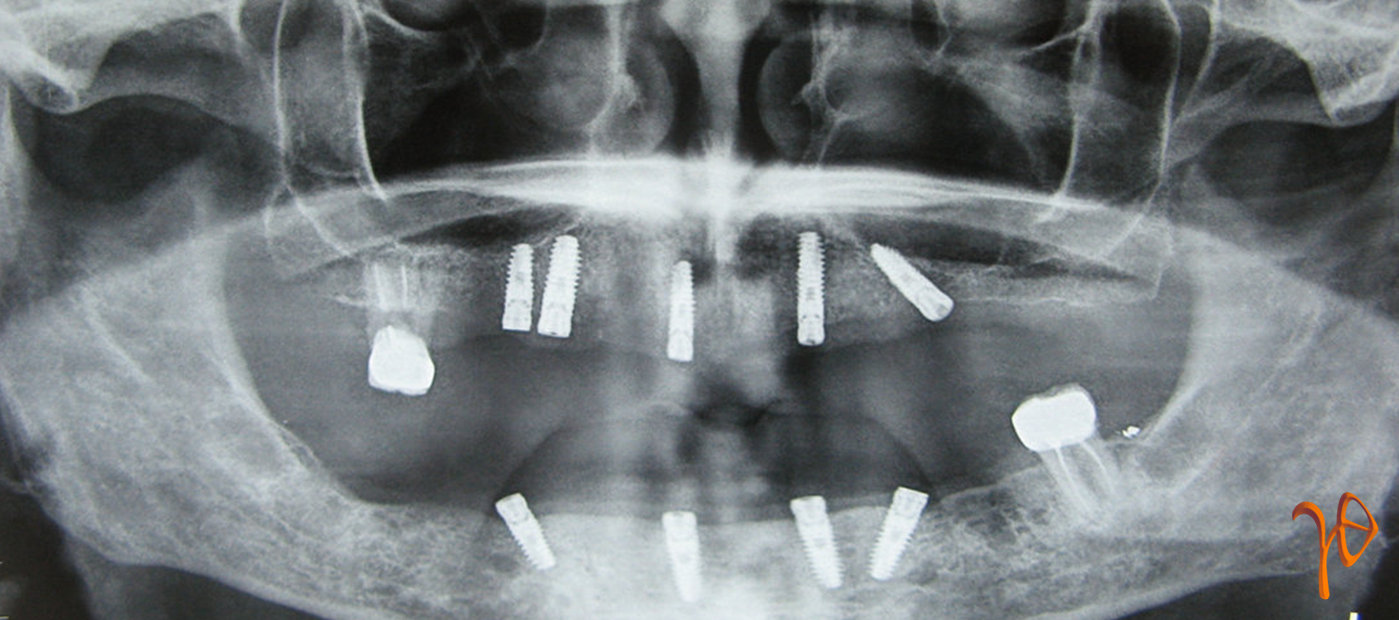

Μετά από πέντε μήνες, ο ασθενής προχώρησε στην προσθετική αποκατάσταση. Για τις θέσεις των εμφυτευμάτων που τοποθετήθηκαν υπό γωνία χρησιμοποήθηκε το σύστημα SMARTFIX (30° angled XiVE MP). Μικρή οστική απορρόφηση σημειώθηκε στις θέσεις #45 και #33 ενδεχομένως λόγω της πίεσης που δεχόταν η περιοχή από την προσωρινή οδοντοστοιχία. Στην άνω γνάθο δεν υπήρχαν προβλήματα(Εικόνες 7, 8 και 9).

Εικόνα 7. Πανοραμική ακτινογραφία, 5 μήνες μετά την τοποθέτηση των οδοντικών εμφυτευμάτων.